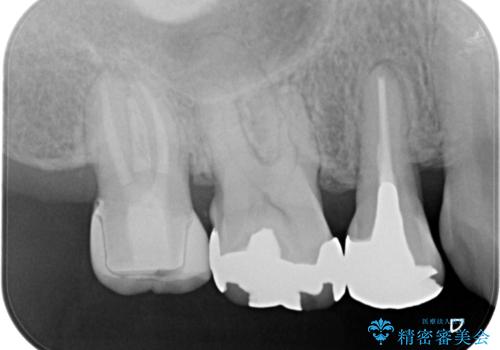

- 古い被せ物をやり変えたいことを主訴に来院されました。

根管治療も行い、きれいな被せ物になり患者さんも喜んでいました。

3本まとめて治療をすることで来院回数を減らし、患者さんの負担を減らすことができ喜んでいただけました。